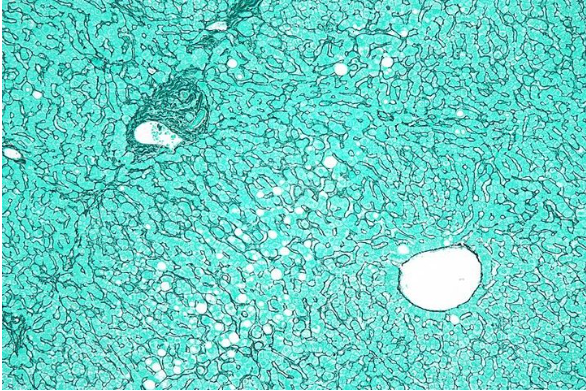

The stain demonstrates reticular fibers of the liver and hence has to be _____ stain.